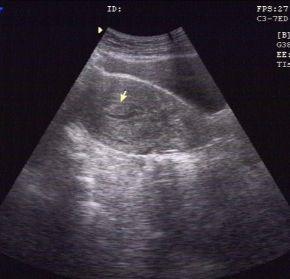

一位24岁,无月经周期、经期和经量的改变。常规体检妇科超声描述:宫腔内见高回声区8mm×5mm,提示:子宫内膜息肉。

一位41岁,有月经经期延长半年,妇科超声描述:宫腔内见高回声区13mm×6mm,提示:子宫内膜息肉。

子宫内膜息肉的无创检查,首选妇科超声检查,推荐经阴道超声(有*生活性**史的女性)或经直肠超声(无*生活性**史的女性)。一般妇科超声检查的时间选择月经周期的第5-7天(早卵泡期)为最佳。但即使超声有上述提示子宫内膜息肉,并不等于确诊。